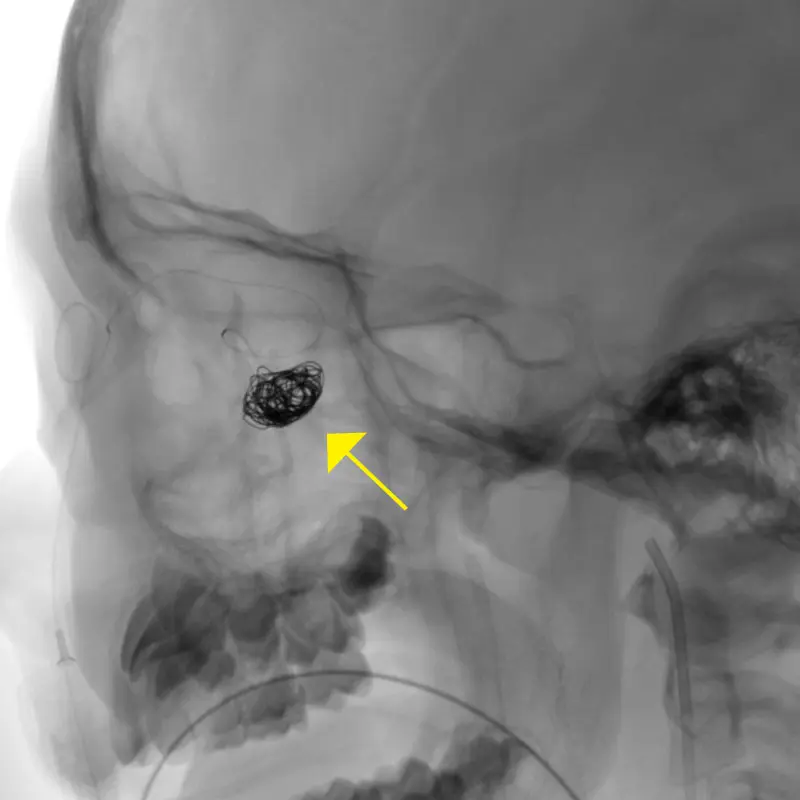

Platinum coil being inserted into the AV fistula (yellow arrow)

Dr. Elmalem’s solution was to avoid any incision by gaining access from the face, through one of the dilated vessels that ran medial to the orbit. While the strategy was sound, its execution proved onerous. Every effort to advance a microcatheter through a facial puncture into the vein to allow treatment of the fistula through coil embolization was met with resistance. “We kept trying different areas of the face, and after an hour and a half were finally successful by going through the angular vein that runs between the side of the nose and inner corner of the eyelid,” explains Dr. Elmalem. That cleared the way for Dr. Fifi and her team to close off the faulty connection between vein and artery with a metallic occluding coil.